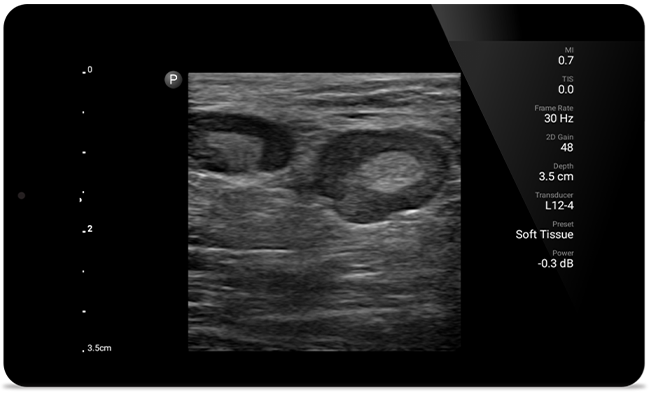

Get the full picture with clear whole-body imagery for a fast, accurate response during MSK examinations.

Lumify L12-4 broadband linear array transducer

• 12 to 4 MHz extended operating frequency range

• Aperture size: 34mm

• 2D, steerable color Doppler, M-mode, advancedXRES and multivariate harmonic imaging, SonoCT

• High resolution imaging for shallow applications: soft tissue, vascular, superficial, musculoskeletal and lung

Padstatic case example image

See more when it counts

From revealing the subtle details of an image to uncovering enriched tissue definition from multiple angles, Lumify can help you make real-time decisions with more confidence from assessment through recovery.